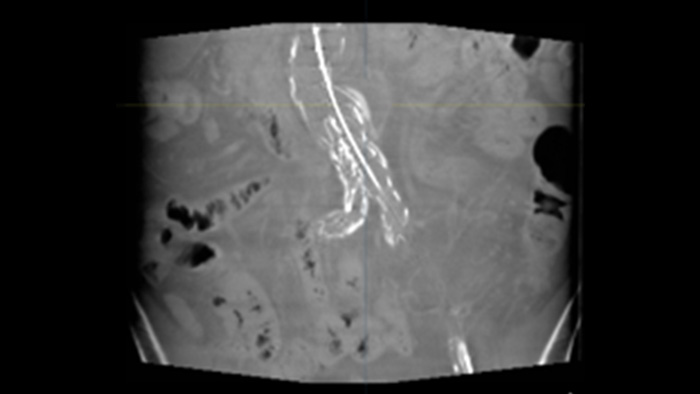

SmartCT Soft Tissue

SmartCT Soft Tissue ist eine Röntgen-Erfassungstechnik, die eine CT-artige Darstellung des Weichgewebes in Relation zu anderen Strukturen erzeugt. Sie kann direkt am Tisch über den Touchscreen gesteuert werden. Mit den CT-artigen Bildern können Weichgewebe, Knochenstrukturen und Stent-Platzierung beurteilt werden.